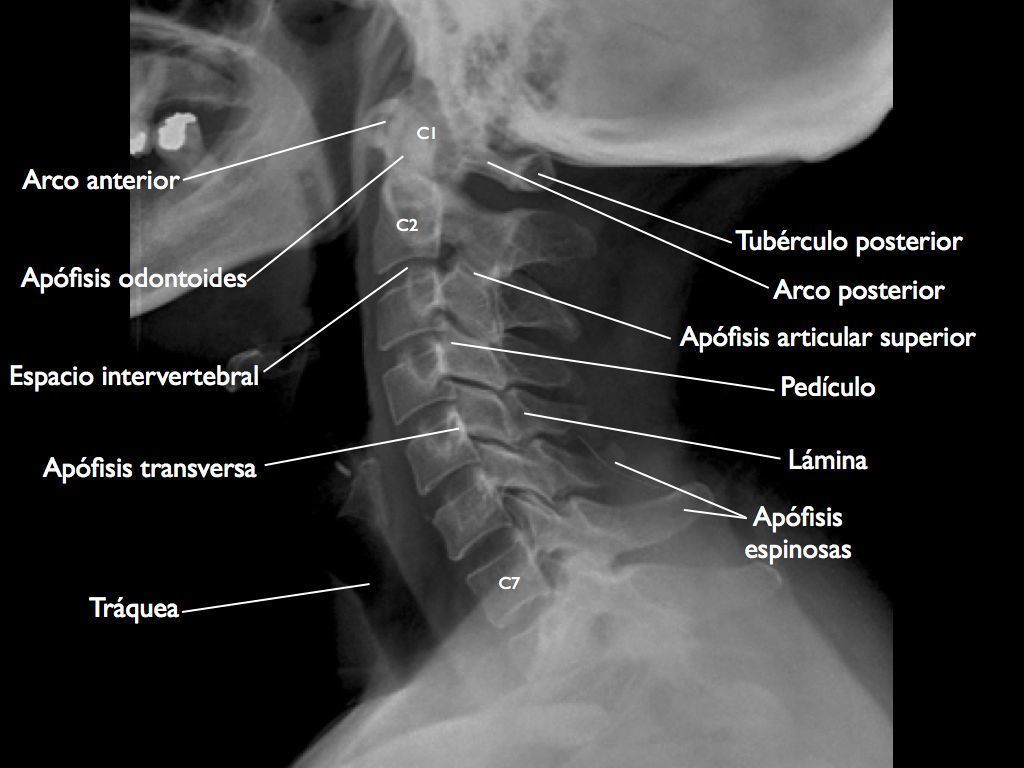

¿Cual es la extensión de la columna cervical alta? De la articulación occipitoatlantoidea al disco C2-C3

¿Cual es la separación radiológica normal entre la odontoides y el arco anterior del atlas? es inferior a 3 mm en el adulto.

¿Como se diagnostican las inestabilidades sagitales? El diagnóstico es radiológico y tomográfico; la lesión, inicialmente invisible, puede revelarse en radiografías dinámicas y/o tardías, *En el niño, una separación de 5 mm es normal